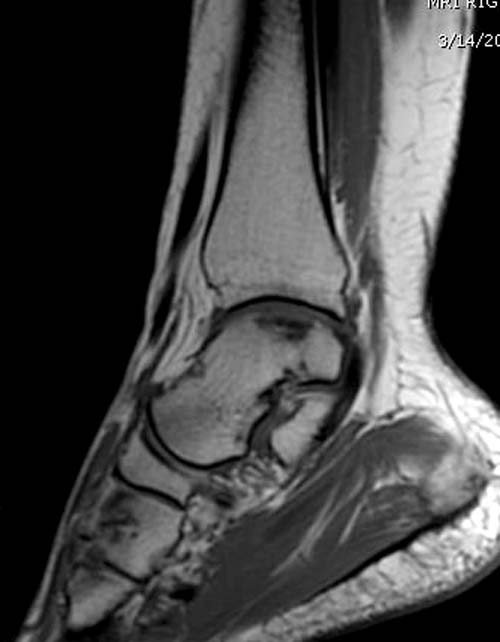

Разбираемый случай не имеет ничего общего с классическим Аваскулярным Некрозом Таранной кости. Здесь так назывемый (osteochondral defect) или osteochondritis dissecans (OCD) таранной кости, при котором патология локализуется в медиально-верхнем нагрузочном отделе. В основном OCD

встречается после хронической травмы, но бывают случаи врожденного генеза, которые обнаруживаются при случайных исследованиях.

Симптоматология  OCD выражается слабым отеком, а более сильные боли наступают после физической нагрузки. В отличие от АВН тарана, когда боли постоянные, а при OCD боли изчезают после отдыха. В начальных стадиях

на рентгенограммах не всегда заметны склерозные участки, и поэтому в большинстве диагноз устанавливается поздно. Приход КТ и МРТ улучшил диагностику, и в срезах внутри кисты можно увидеть жидкость, но это не означает проявление симптоматологии. Симптомы проявляются с момента образования внутрисуставных краевых фрагментаций!

Имя     : 6 OCD MRI.jpg

Тип     : image/jpg

Размер  : 23981 байтов

Описание: отсутствует

Url     : http://weborto.net:8080/pipermail/ortho/attachments/20120408/bb356219/attachment-0017.jpg

Вложение не в текстовом формате было извлечено…

Имя     : 7 OCD MRI.jpg

Размер  : 25582 байтов

Url     : http://weborto.net:8080/pipermail/ortho/attachments/20120408/bb356219/attachment-0018.jpg

Имя     : 8 OCD MRI.jpg

Размер  : 40549 байтов

Url     : http://weborto.net:8080/pipermail/ortho/attachments/20120408/bb356219/attachment-0019.jpg

Имя     : 10 OCD MRI.jpg

Размер  : 33644 байтов

Url     : http://weborto.net:8080/pipermail/ortho/attachments/20120408/bb356219/attachment-0020.jpg